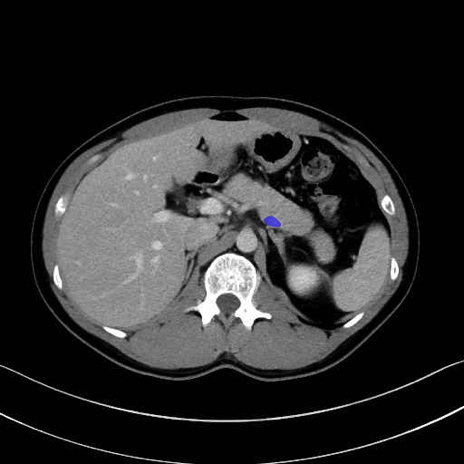

脾静脈の画像解剖

■起始:脾門で脾静脈枝が合流して本幹を形成。

■走行:膵体尾部の後面溝を右走し、膵頸部の後方で上腸間膜静脈(SMV)と合流して門脈を形成。

■主な流入枝:短胃静脈・左胃大網静脈・膵静脈、そして下腸間膜静脈(IMV)(変異あり)。